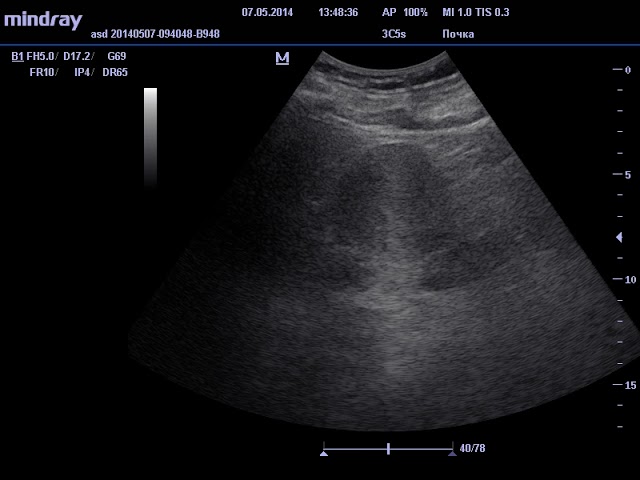

Почки и мочеточники

УЗИ почек часто назначается отдельно от УЗИ остальных органов. Это исследование помогает выявить нарушения работы органа, опухоли, наличие камней и другие неприятные заболевания. Нормальные параметры почки должны быть примерно такие:

- Размер – 5*6*12 см, толщина паренхимы, то есть внешней оболочки – до 25 мм. Одна почка может быть немного больше другой, но не более чем на 2 см;

- Структура ровная, контуры четкие, эхогенность на уровне печени или чуть ниже;

- Подвижность при дыхании – не более 3 см.

Вместе с почками врач может осмотреть мочеточники и надпочечники. В них не должно быть новообразований, камней и песка.